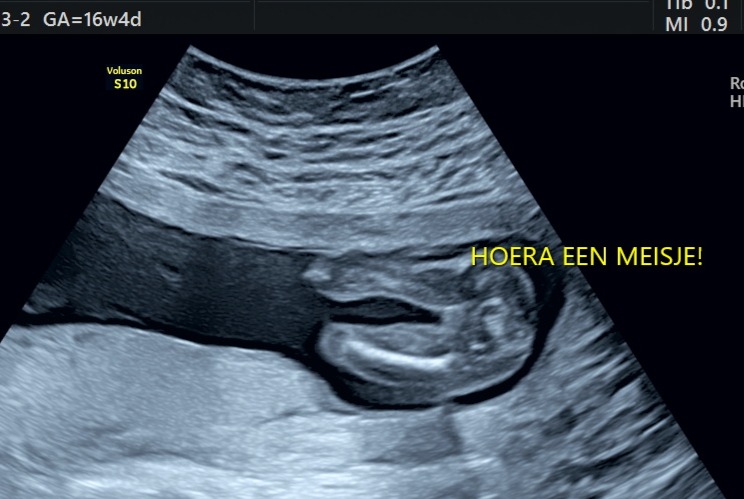

Wil je weten of je een jongen of een meisje kunt verwelkomen, dat kan! De geslachtsbepaling kun je bij ons vanaf 13+2 weken zwangerschap inplannen, je kunt het dan met ongeveer 98% zeker weten. Heb je net een weekje meer geduld, vanaf 14+5 weken is het bepalen van het geslacht voor 99,9% zeker.

Elk kind ontwikkelt zich anders, en soms is het ongeacht het aantal weken nog net iets te vroeg om te zeggen of het een jongen of een meisje is.

Vroege 2D geslachtsbepaling

Vanaf 13+2 weken tot 14+2 weken 10-15 min, inclusief 2 zwart/wit foto afgedrukt. We zijn expert in het uitvoeren van deze vroege geslacht echo, door oa. onze ervaring en de goede gedetailleerde echo machine. We kunnen het geslacht direct met je delen we kleuren dan de hele kamer roze of blauw, maar we kunnen natuurlijk ook het geslacht op een briefje zetten zodat je het later zelf kunt bekijken of kunt doorgeven voor een gender reveal feestje. Wij kunnen het ook voor je doorbellen/mailen. Naast het beoordelen van het geslacht blijft er genoeg tijd over om samen naar jullie kleintje te kijken!

Standaard 2D geslachtsbepaling

Vanaf 14 weken 10 -15 min, inclusief 2 zwart/wit foto’s afgedrukt, we kunnen het geslacht direct met je delen we kleuren dan de hele kamer roze of blauw, maar we kunnen natuurlijk ook het geslacht op een briefje zetten zodat je het later zelf kunt bekijken of kunt doorgeven voor een gender reveal feestje. Wij kunnen het ook voor je doorbellen/mailen. Naast het beoordelen van het geslacht blijft er genoeg tijd over om samen naar jullie kleintje te kijken!